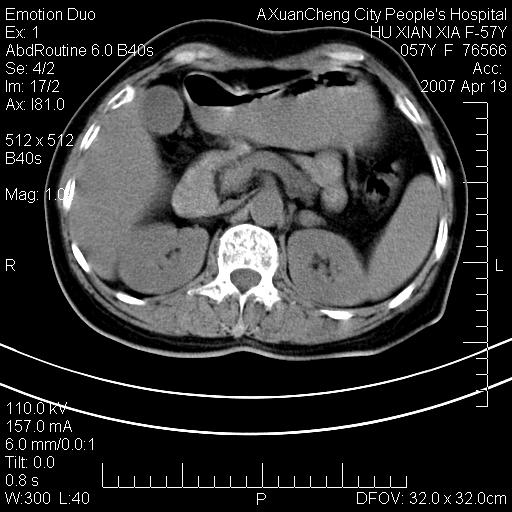

标题: CT7778:[原创]F,57Y腹痛待查,胸片提示肺部占位,应当很典型 [打印本页]

标题: CT7778:[原创]F,57Y腹痛待查,胸片提示肺部占位,应当很典型

胸片提示肺部占位

双侧肾上腺及腹膜后淋巴结增大,考虑转移,建议查原发灶.

降结肠有无问题?双侧肾上腺占位

双侧肾上腺增大,有分叶,密度均匀,考虑转移建议查原发灶

1.双侧肾上腺占位,转移首先考虑。

3.12指肠水平段狭窄,建议行低张12指肠造影。

双侧肾上腺及腹膜后淋巴结增大,考虑转移,肺转移?

双侧肾上腺结节样肿块,结合肺部肿块,考虑肺癌肾上腺转移。

双侧肾上腺及腹膜后淋巴结增大,结合胸片提示肺部占位,考虑肺癌双侧肾上腺及腹膜后淋巴结转移.